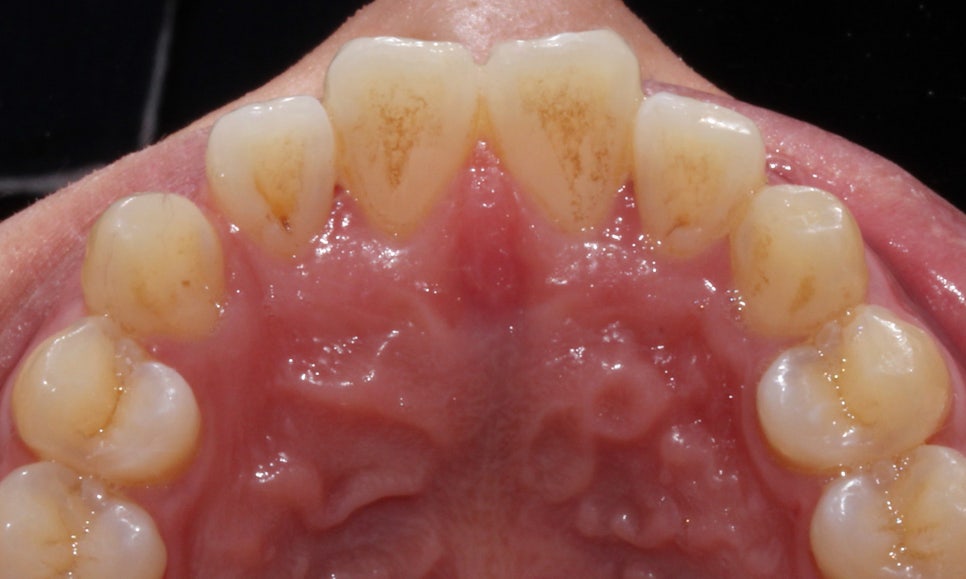

앞니의 경우 뻐드러짐이 심해서

바깥 방향으로 치아들이 누워있는 모양인데요,

아랫니는 치열이 고르지 못하고

들쭉날쭉하게 배열되어 있어

이를 교정하기 위해 2D교정을 시작했습니다!